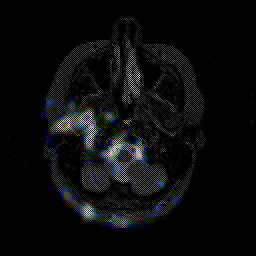

Glioblastoma multiforme overlay -- Slice #9

[Home][Help][Clinical][Tour 1][Tour 2][Tour 3] Slice 9